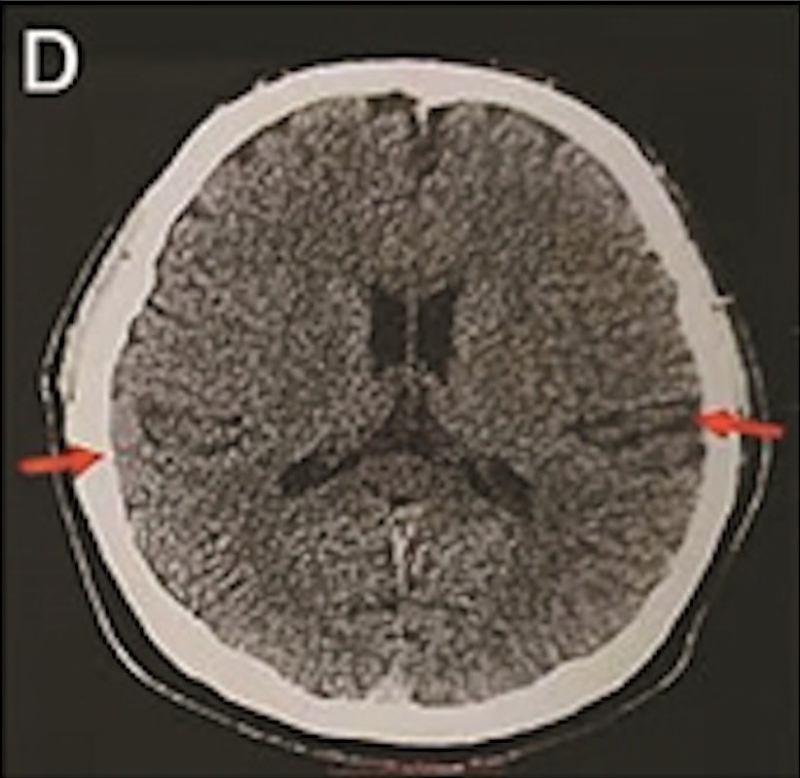

最年轻的19岁阿兹海默症男子脑部扫描结果:

▲19岁阿兹海默症(认知障碍症/脑退化症)男子脑部扫描结果。北京青年报

该名19岁男子到医院接受多项检查,包括脑脊液指标检测及正电子扫描。结果显示,他出现轻度脑萎缩等症状,最终被临床诊断为“阿兹海默症”。